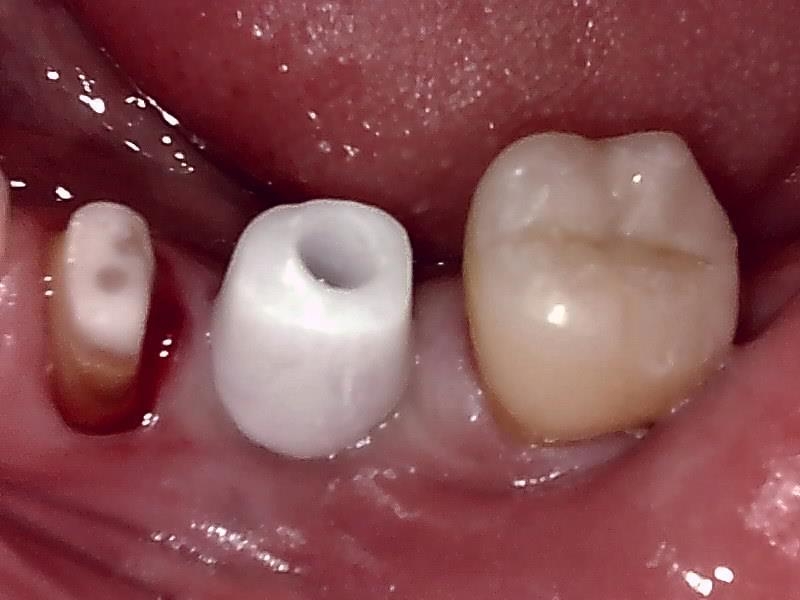

インプラントの上部構造 (左下)

(ジルコニアセラミッククラウン)